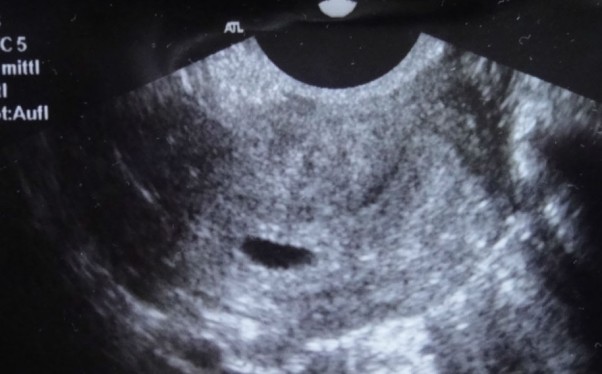

5 tydzień <3

byłam na usg z twoim tatusiem przy się upewnić że dwie kreseczki to nie wymysł mojej wyobraźni :) i pani doktor powiedziała ze nie mam zwidów bo pod moim sercem zaczyna już bić Twoje :) szczęście ogromne nie da się opisać jakie...jestem z nami naszą częścią naszą wielką Miłością <3